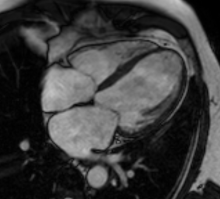

***除了心脏超声波之外 , 还可以通过心脏核磁共振来检查 。

文章插图

↑非常美丽的心脏核磁共振图像